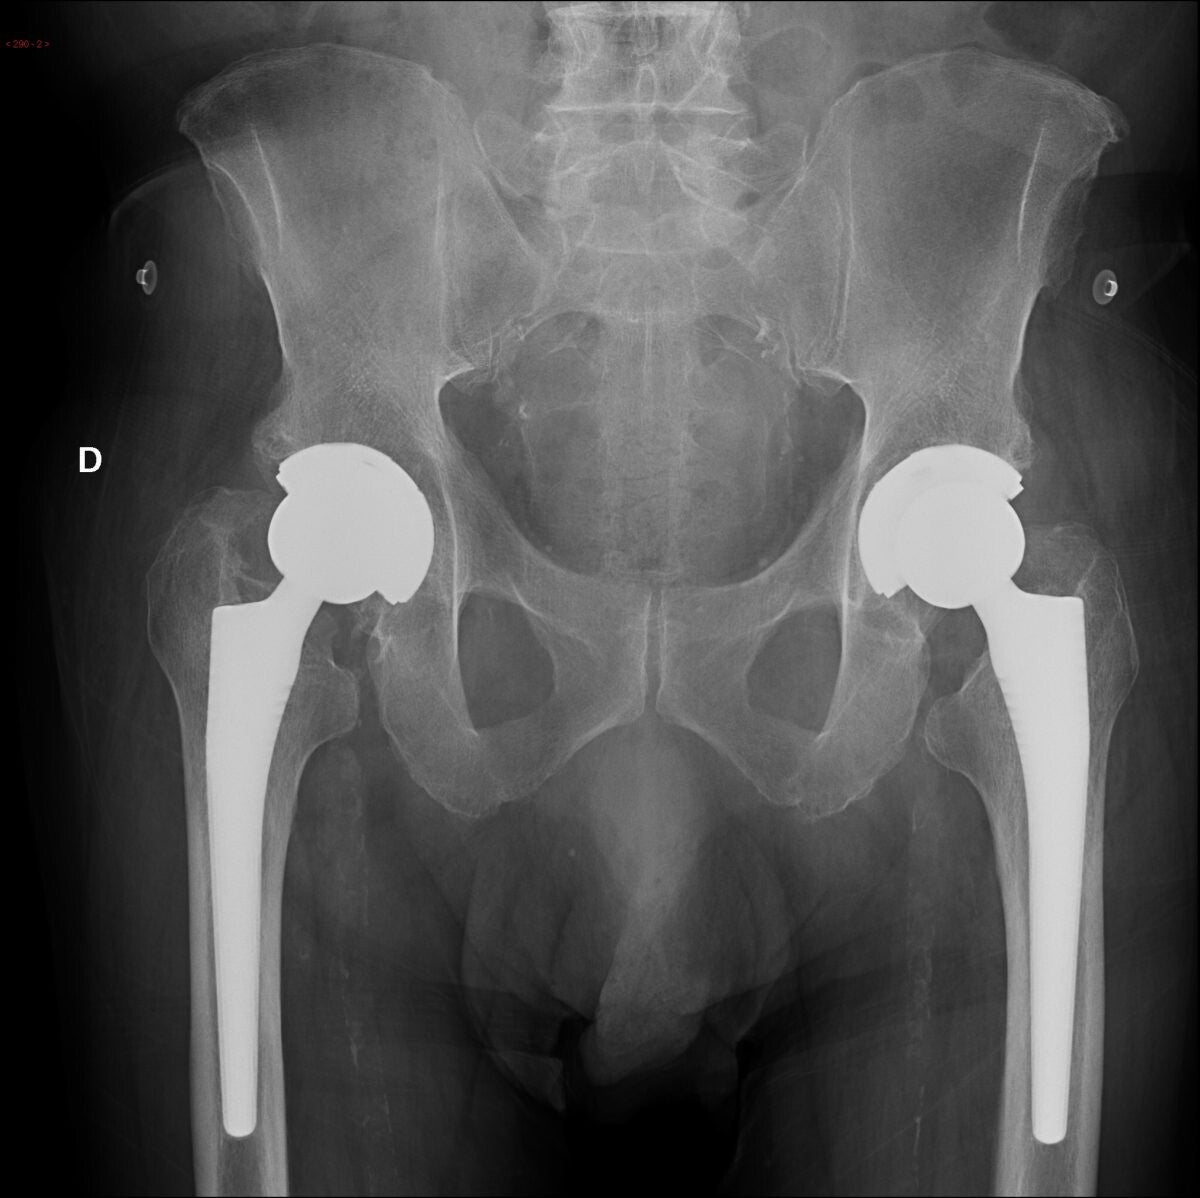

Protesi d’anca: il valore del planning pre-operatorio e il ruolo delle cupole a doppia mobilità

La chirurgia protesica d’anca rappresenta oggi una delle più grandi conquiste dell’ortopedia moderna. Quando il dolore compromette la libertà di movimento, limita l’autonomia e riduce la qualità della vita, la sostituzione protesica può offrire un recupero concreto e duraturo.

Ma una protesi d’anca ben riuscita non dipende soltanto dal gesto chirurgico. Dietro ogni buon risultato esiste uno studio accurato del paziente, della sua anatomia, delle sue esigenze funzionali e dei possibili fattori di rischio.

È in questa fase che il planning pre-operatorio assume un ruolo centrale: non come semplice formalità tecnica, ma come fondamento di una chirurgia precisa, personalizzata e biomeccanicamente corretta.

All’interno di questa visione moderna e su misura, anche l’impiego di cupole a doppia mobilità trova uno spazio sempre più rilevante nei pazienti selezionati, soprattutto quando il tema della stabilità articolare diventa prioritario.